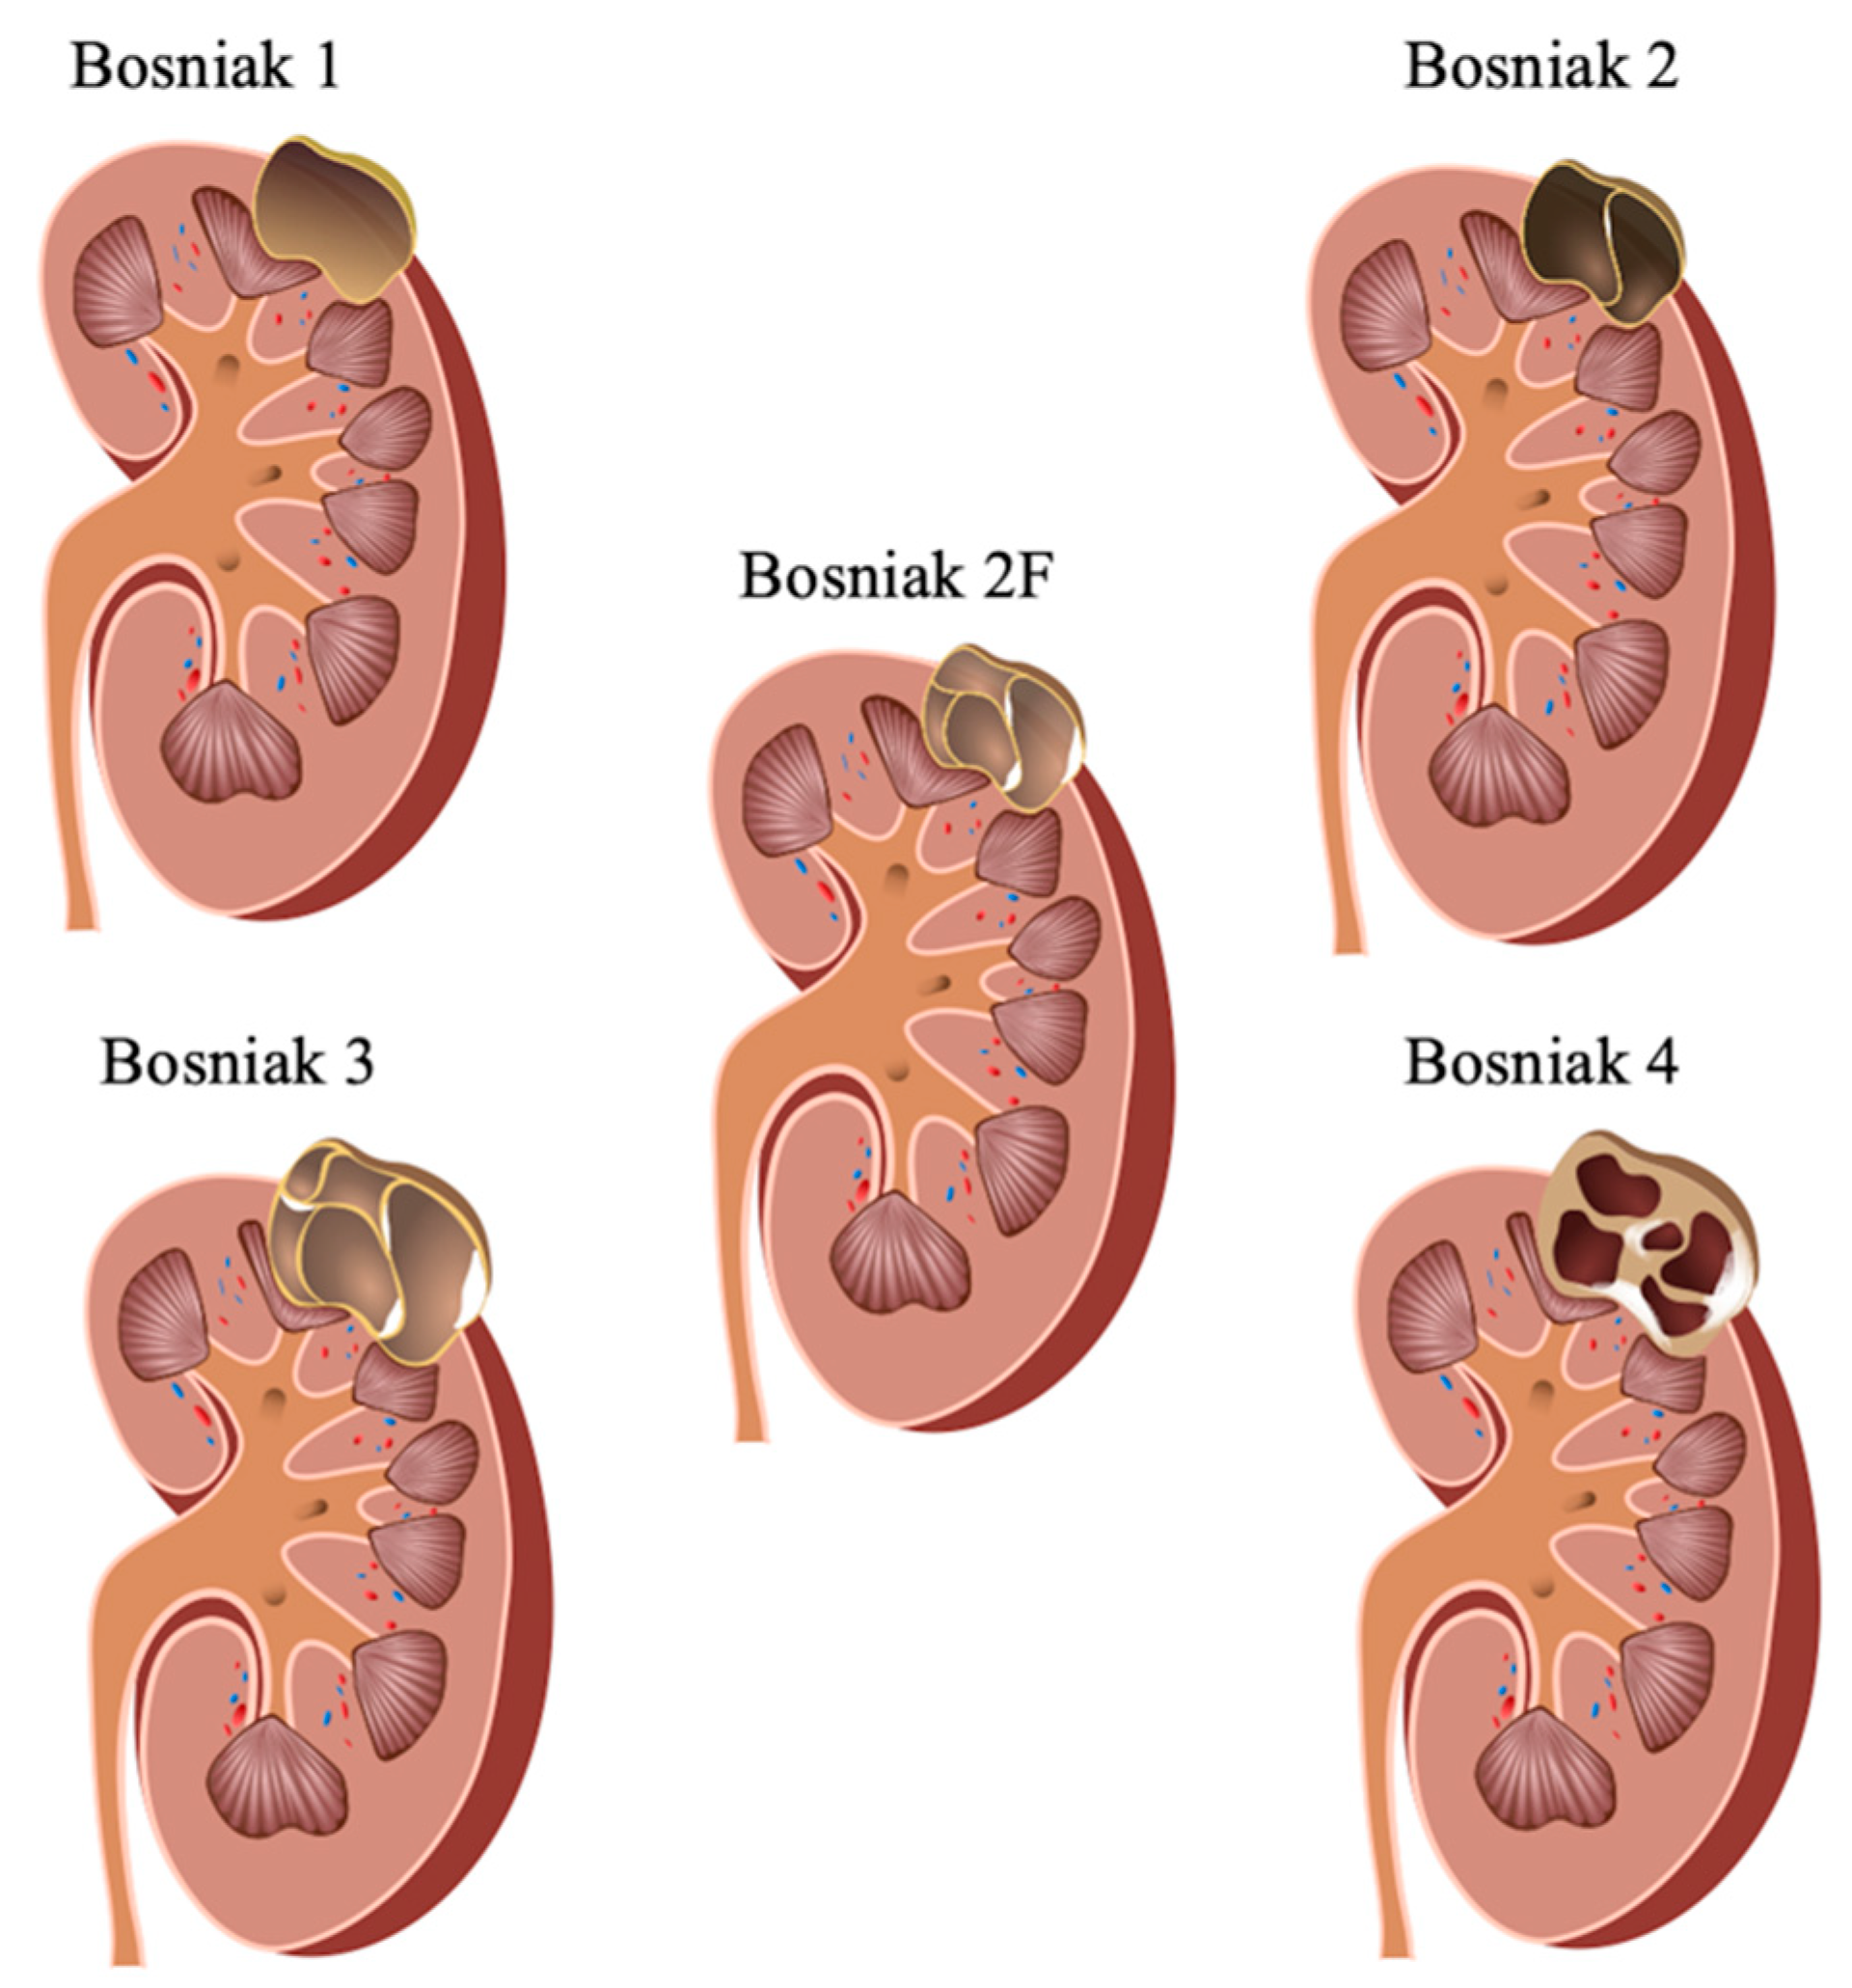

- Bosniak, M.A. Problems in the radiologic diagnosis of renal parenchymal tumors. Urol. Clin. N. Am. 1993, 20, 217–230. [Google Scholar]

- Bosniak, M.A. The current radiological approach to renal cysts. Radiology 1986, 158, 1–10. [Google Scholar] [CrossRef] [PubMed]

- Bosniak, M.A. Diagnosis and management of patients with complicated cystic lesions of the kidney. AJR Am. J. Roentgenol. 1997, 169, 819–821. [Google Scholar] [CrossRef] [PubMed]

- Bosniak, M.A. The use of the Bosniak classification system for renal cysts and cystic tumors. J. Urol. 1997, 157, 1852–1853. [Google Scholar] [CrossRef]

- Rubenthaler, J.; Bogner, F.; Reiser, M.; Clevert, D.A. Contrast-Enhanced Ultrasound (CEUS) of the Kidneys by Using the Bosniak Classification. Ultraschall Med. 2016, 37, 234–251. [Google Scholar] [CrossRef]

- Silverman, S.G.; Pedrosa, I.; Ellis, J.H.; Hindman, N.M.; Schieda, N.; Smith, A.D.; Remer, E.M.; Shinagare, A.B.; Curci, N.E.; Raman, S.S.; et al. Bosniak Classification of Cystic Renal Masses, Version 2019: An Update Proposal and Needs Assessment. Radiology 2019, 292, 475–488. [Google Scholar] [CrossRef]